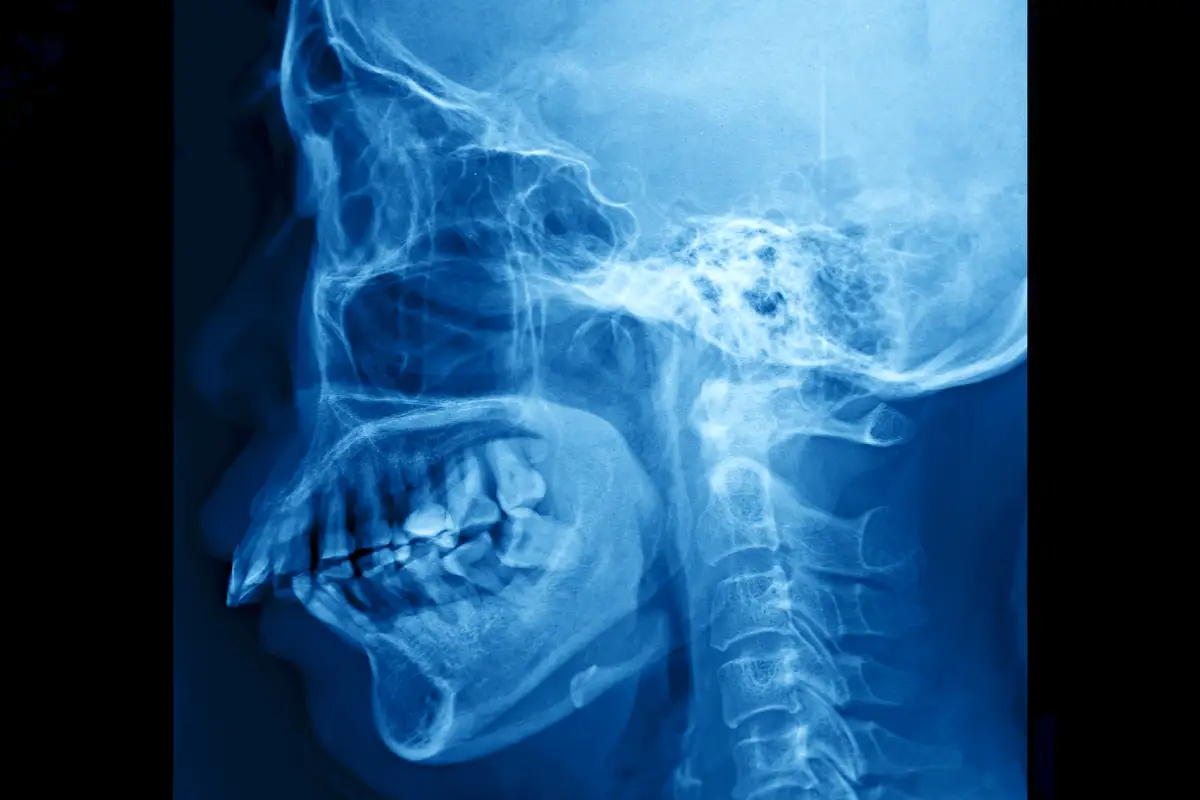

When most patients think about complications from a tooth extraction, “dry socket” is one of the more dreaded possibilities.